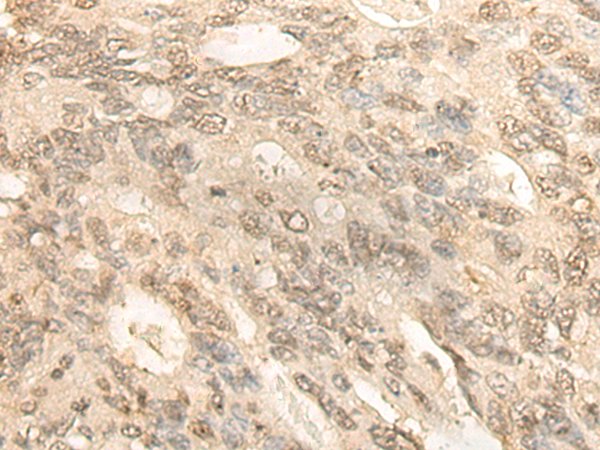

IHC positive control:

Human lung cancer and Human colorectal cancer

IHC Recommend dilution:

30-150